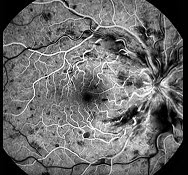

该图是何种疾病的荧光造影图()

A . 视网膜中央动脉阻塞

B . 视网膜中央静脉阻塞

C . 视网膜分支动脉阻塞

D . 视网膜分支静脉阻塞

E . 视网膜静脉周围炎

[单选题]该图是何种疾病的荧光造影图()A.视网膜中央动脉阻塞B.视网膜中央静脉阻塞C.视网膜分支动脉阻塞D.视网膜分支静脉阻塞E.视网膜静脉周围炎